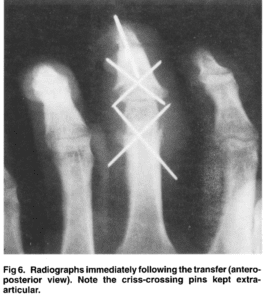

homodigital island transfer

Distal interphalangeal joint to proximal interphalangeal joint homodigital island transfer…